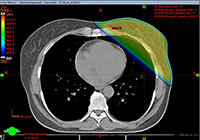

Diese Technik kann insbesondere bei der Bestrahlung der linksseitigen Brust bzw. Brustwand angewendet werden, um die Dosisbelastung an den benachbarten Risikoorganen weiter abzusenken. Durch die natürliche Bewegung der Brustwand bei Einatmung vergrößert sich bei den meisten Patienten der Abstand zwischen Brustwand und Herz. Aufgrund des größeren Abstandes wird weniger Dosis im Herzen und insbesondere in bestimmten Bereichen der Koronargefäße (RIVA) appliziert. Eine große klinische Studie hat gezeigt, dass mit einer Verringerung der Dosis auch das Risiko einer Herzerkrankung als Spätfolge der Bestrahlung signifikant reduziert werden kann. Da diese Spätfolgen erst nach sehr langer Zeit auftreten können (im Bereich von ca. 20 Jahren) profitieren besonders jüngere Patienten (<60 Jahre) von dieser Technik. Ergänzt werden muss an dieser Stelle, dass das Risiko einer bestrahlungsbedingten Herzerkrankung generell sehr gering ist. Einzelheiten hierzu werden Ihnen im individuellen Aufnahmegespräch bei Ihrem Facharzt mitgeteilt.

Im nachfolgenden Bild sehen Sie, wie sich der Abstand zwischen Herz und Bestrahlungsregion bei tiefer Einatmung vergrößert. Auch der Anteil der bestrahlten Lunge nimmt bei tiefer Einatmung ab.

Gegenüberstellung des Effekts der Bestrahlung bei tiefer Einatmung

Links: Bestrahlung in normaler Atemlage – das Herz und insbesondere der sogenannte RIVA befinden sich in unmittelbarer Nähe der Bestrahlungsregion.

Rechts: Bestrahlung bei tiefer Einatmung – das Herz (und RIVA) liegen weit entfernt von der Bestrahlungsregion.